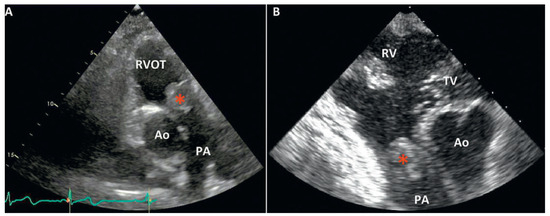

Pulmonary artery sarcomas are uncommon intracardiac tumours with poor prognosis. We report the case of a 69-year-old woman in good health presenting with rapidly progressive dyspnoea and an unfamiliar systolic murmur. Echocardiography revealed pulmonary valve stenosis due to an obstructing mobile mass. Imaging [...] Read more.

Pulmonary artery sarcomas are uncommon intracardiac tumours with poor prognosis. We report the case of a 69-year-old woman in good health presenting with rapidly progressive dyspnoea and an unfamiliar systolic murmur. Echocardiography revealed pulmonary valve stenosis due to an obstructing mobile mass. Imaging studies confirmed the presence of a contrast-enhancing lesion adherent to the valve, extending into the pulmonary trunk and right ventricular outflow tract, and suggestive of malignancy. Endovascular biopsy was attempted with no success. Surgical resection with autologous graft valve replacement and pulmonary artery reconstruction was performed. Postoperative histological examination confirmed the diagnosis of an undifferentiated pleomorphic sarcoma. Pulmonary artery sarcoma should be considered as a rare differential diagnosis in patients presenting with dyspnoea and a crescendo–decrescendo systolic murmur increasing with inspiration. Echocardiography is a useful first diagnostic approach but multi-imaging assessment is almost always necessary for definite diagnosis. Our case provides insights into the challenges met by cardiologists, radiologists and cardiac surgeons in the management of such cases. Full article

Show Figures

Figure 1